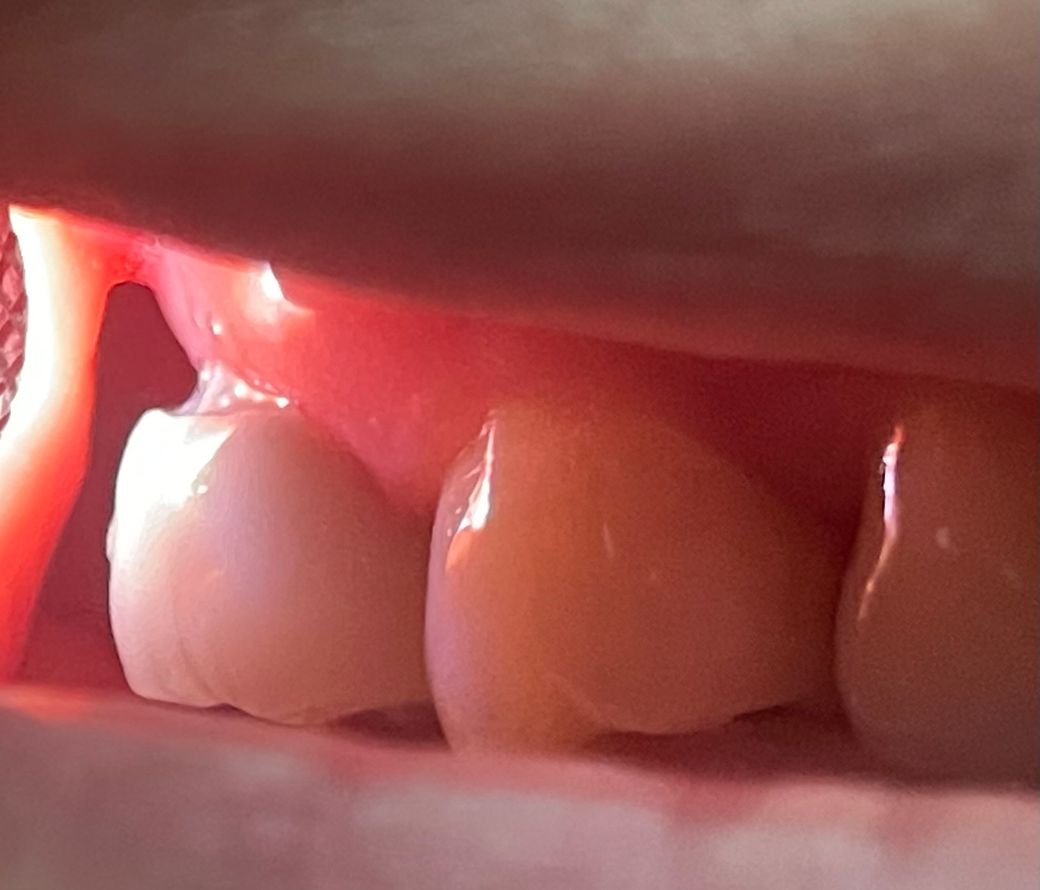

어제 어금니 크라운을 씌웠는데 혀 닿는쪽 면은 크라운과 잇몸이 매끄럽게 잘 연결되어있고 걸리는 것도 없습니다. 그런데 볼 닿는 쪽 면은 크라운과 잇몸 사이에 틈이 있고 만져보면 손톱도 걸리고, 치실도 틈에 걸리면서 내려옵니다. 저걸 치은연상마진이라고 볼 수 있나요? 크라운을 다시 제작해야하나요? 사이로 음식물이 끼여 크라운 안쪽으로 2차 충치가 생기지 않을지 걱정됩니다

어제 셋팅하신 크라운이 저렇게 떠잇다면 다시 크라운을 제작하셔서 셋팅하시는게 좋을것같습니다.

제작한지 얼마 안되었다면 잇몸퇴축의 문제는 아니고 크라운 재제작이 필요할 것 같습니다 저 상태로는 말씀하신것처럼 음식물이 잘 낄 것 같습니다

현재 상태로서는 해당 보철물을 다시 제작해야 할 수도 있어 보입니다. 치은 연상 마진인지는 현재 사진만으로는 알 수 없고 explorer 등으로 긁어보아야 합니다. gap이 있으므로 치과 방문 후 다시 검사를 해보시는 것이 좋습니다.